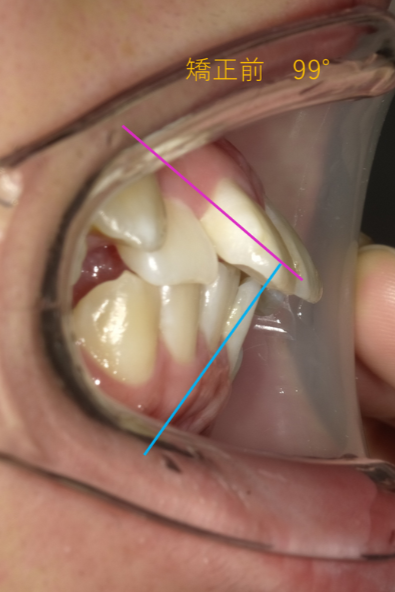

| 治療前の症状 | 上下切歯の傾斜が大きい症例Interincisal angle 99° |

注目していただきたいのは前歯の角度です。

上下の前歯が作る角度(インターインサイザルアングル)が99°でした。

99度ってどうなの?」と思われるかもしれませんが、理想的な美しさとされる角度は約120度〜130度と言われています。つまり、99度というのは「前歯がかなり外側にパタンと倒れて、突き出している状態」なんです。

この角度が深くなる(120〜130度に近づく)ことで、唇がスッと中に入り、横顔のEラインが整います。数字で見ると、矯正でどれだけ歯の土台から角度が変わったかが一目瞭然です。